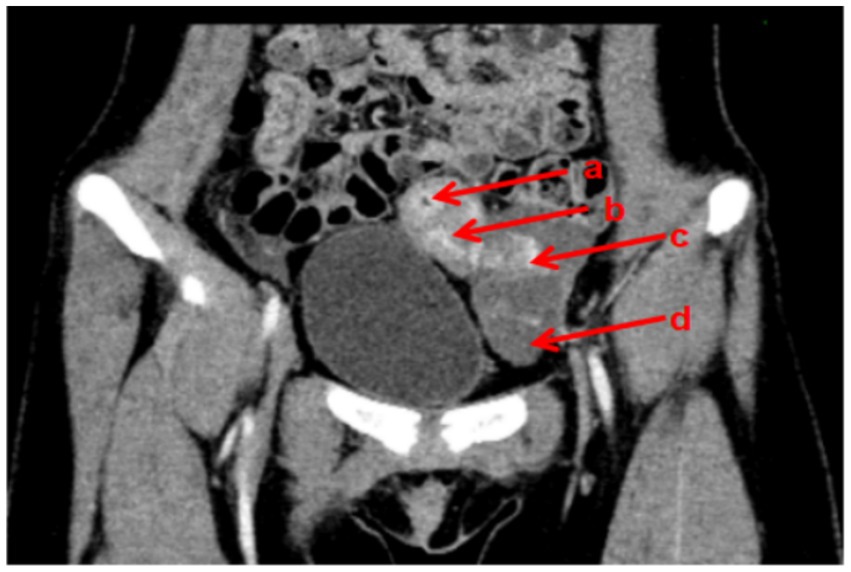

You don't have a Frontiers account ? You can register here

Abstract Introduction: Menstruation marks a significant developmental milestone, typically indicating healthy and normal pubertal changes in females. Primary amenorrhea can arise from various causes, including outflow tract abnormalities, resistant endometrium, primary ovarian insufficiency, and disorders of the hypothalamus, pituitary gland, or other endocrine organs. This report presents an exceptionally rare Müllerian malformation that does not conform perfectly to existing classification systems, necessitating an individualized management approach. Case presentation: We present the case of a 12-year-old girl with a rare Müllerian malformation, who presented with cyclic lower abdominal pain persisting for over nine months, with acute exacerbation in the preceding day. Comprehensive clinical evaluation and preoperative pelvic CT imaging revealed multiple anomalies: an unilateral rudimentary horn uterus with cavity and unilateral absence of the ovary and fallopian tube. Digital 3D CT reconstruction was utilized to confirm the diagnosis, revealing a left rudimentary horn uterus with cavity, hydrosalpinx of the left fallopian tube, and absence of the right ovary, fallopian tube and hemi-uterus. Surgical management included laparoscopic resection of the left rudimentary horn uterus and left fallopian tube. Postoperatively, the patient achieved complete resolution of cyclic lower abdominal pain. Conclusions: Digital 3D CT reconstruction technology is instrumental in diagnosing rare Müllerian malformations, providing crucial anatomical insights for surgical planning and patient counseling.